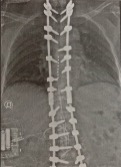

MULTIDISCIPLINARY MANAGEMENT OF REFRACTORY FAILED BACK SURGERY SYNDROME: A COMPLEX CASE REPORT WITH MULTIMODAL INTERVENTIONS AND LITERATURE REVIEW

D. Gemma1, G. Pulito2 | 1"Cardinale G. Panico" Hospital, Tricase (Lecce); 2"V. Fazzi" Hospital, Lecce